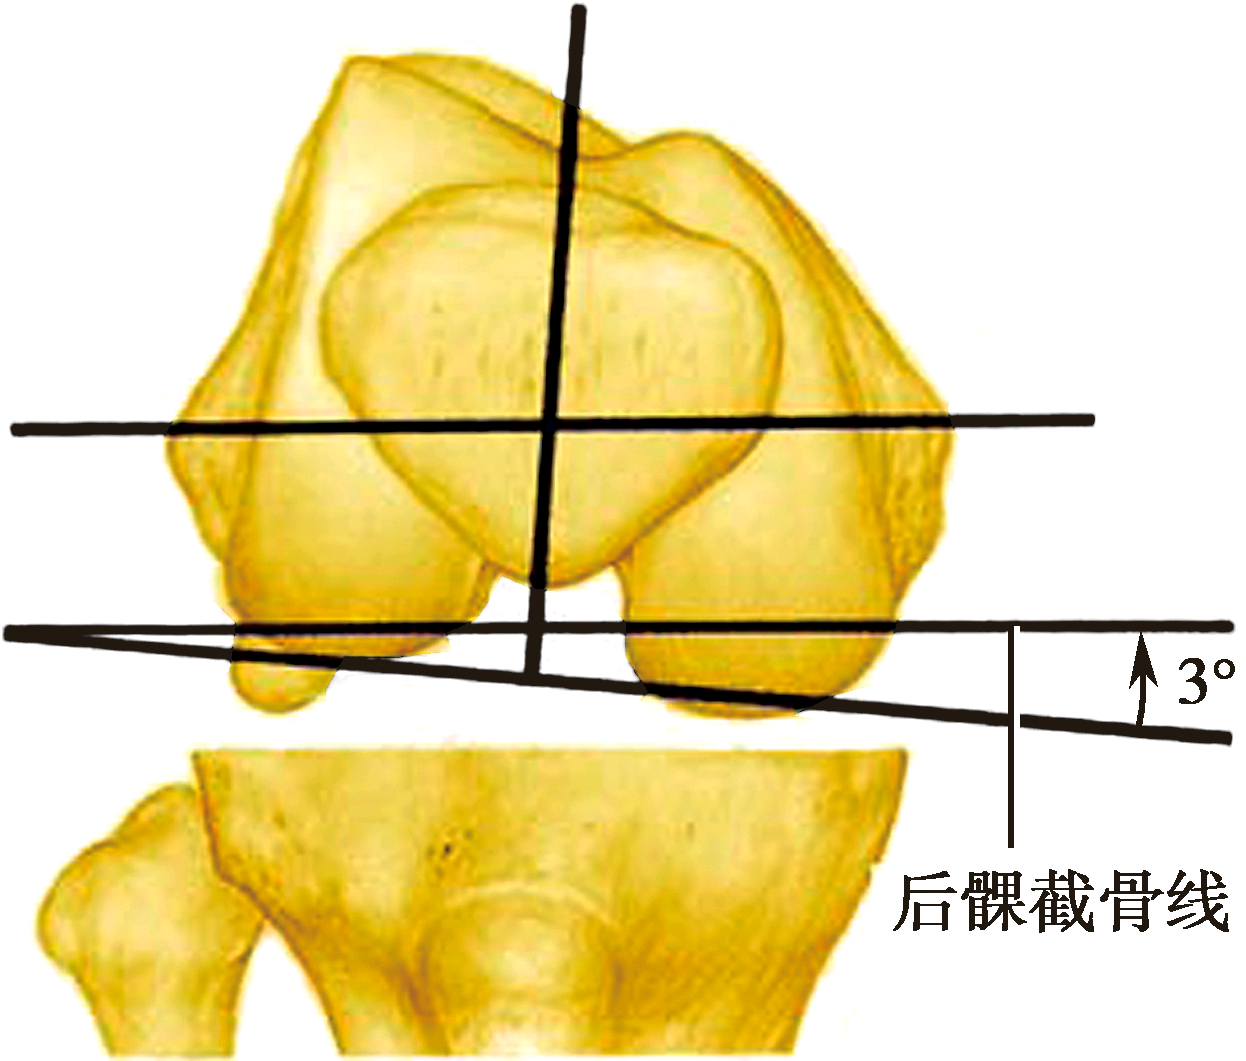

股骨后髁外旋3°截骨,以获得矩形的屈曲间隙

正常胫骨平台有3°~5°内倾,现代膝关节假体设计通常将胫骨假体与胫骨解剖轴垂直,从而忽略了解剖上存在的内翻。这样当膝关节屈曲时,要求股骨假体也相应外旋3°~5°安放,即多切除一些股骨内髁后方的骨质,以保证获得矩形的屈曲间隙和内外侧韧带张力相等。如果股骨后髁内外侧对称切骨,屈曲间隙将成为梯形,假体植入后,屈膝位外侧副韧带较为松弛,引起关节外侧不稳定。另外,适当外旋股骨假体,可使髌骨滑车沟向前外侧旋转,减少Q角及髌骨向外脱位的倾向。